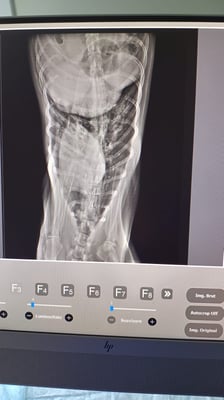

Doch dann erkannte unsere liebe Grig endlich die Ursache für ihren schlechten Zustand: Das arme Mädchen war voller Herzwürmer! Ein Röntgenbild und eine Ultraschallaufnahme zeigten das wahre Ausmaß der Situation.

But then our dear Grig finally recognized the cause of her terrible condition: the poor girl was full of heartworms! An x-ray and an ultrasound showed the true extent of the situation.